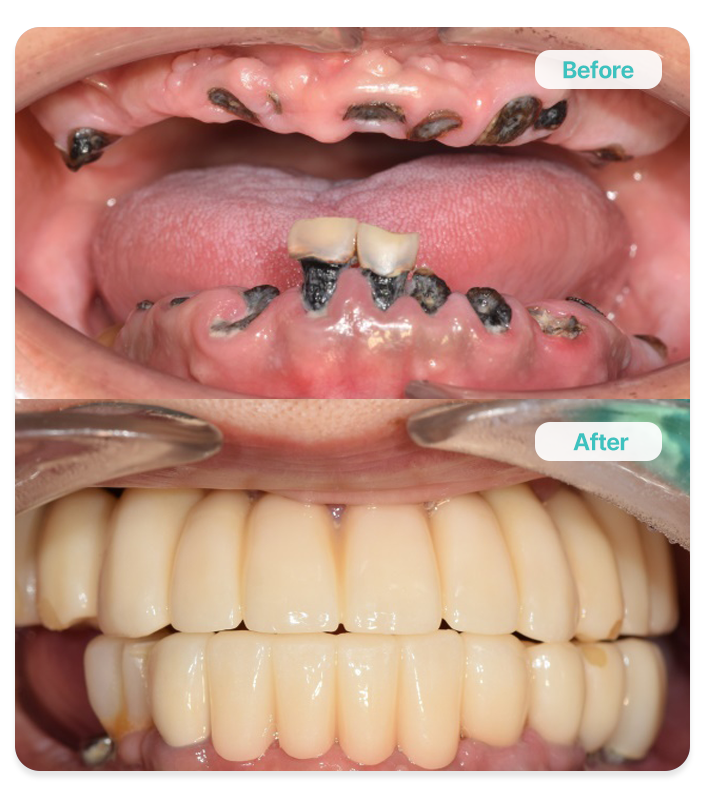

Full-Mouth Dental Implants

전악 임플란트

다수의 치아를 상실했을 때 임시 보철을 사용하여 발음 및

저작 기능을 미리 평가하고, 최종 보철물을 수복하여

구강 기능 회복을 위한 과정을 진행하는 치료입니다.

전체 치아 대체

All-on-4/6

잃어버린 구강 기능 회복